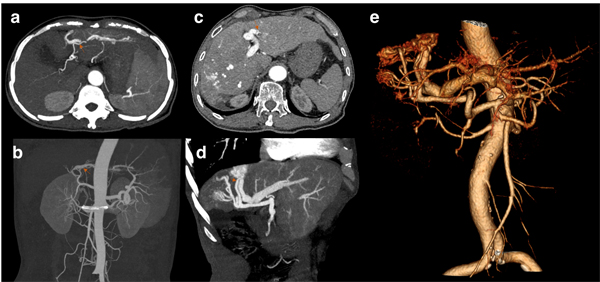

Rebleeding was defined as new onset of hematemesis, coffee-ground vomitus, hematochezia, or melena according to the guideline [6]. Early diagnosis of IAPF was described as the diagnosis of IAPF before or 7 days within the first bleeding episode. A peripheral type of IAPF was defined as a fistula located under the right/left branches of the portal vein, and a central type of IAPF was defined as a fistula located in the main portal vein. However, in a diffuse type of IAPF, fistulas involved both the main portal vein and branches in the liver. Based on the severity, IAPFs in the present study were classified into two groups, mild and severe, by the extent of the early enhancement of peripheral portal vein branches and the presence of wedge-shaped, transient peripheral areas of enhancement in the arterial phase, as previously described by Guzman and Choi et al [7][8]. Figure 1 demonstrates the CT angiography of patients with IAPF.

Figure 1: Figure a and b are from the same patient and demonstrate the mild type of IAPF. a. The arterial phase of dynamic CT shows early enhancement of transient, peripheral, small hepatic vein branches. b. Maximal intensity projection (MIP) image of the portal trunk in the arterial phase shows the mild type of fistula. Figure c, d, and e are from the same patient and demonstrate the severe type of IAPF. c. Multiple fistulas developed in both central and peripheral areas. d. A large fistula was seen in the MIP image. e. Volume-rendered images show multiple fistulas in a severe type of IAPF. (Red arrows for concomitant hepatic arteries).